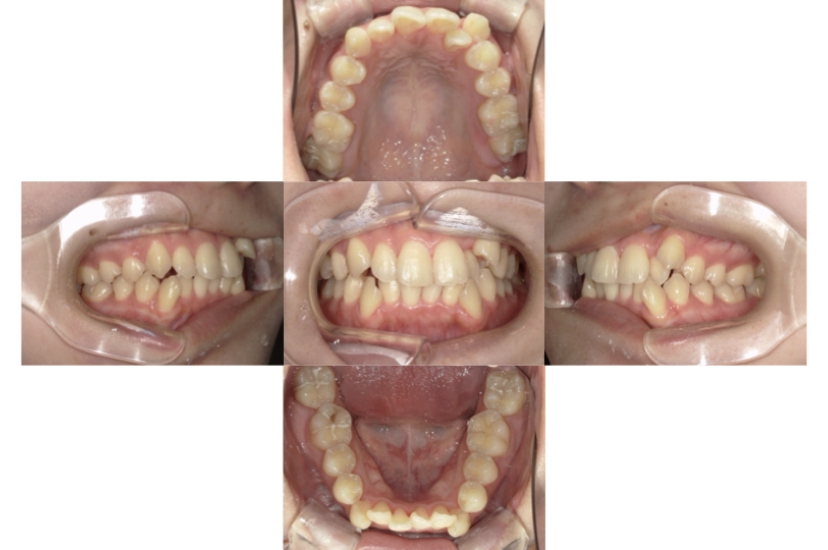

症例2

上下顎前突、叢生

抜歯

ブラケット矯正

上下顎前突、叢生(上下出っ歯、上下の前歯のガタガタ)のケースです。

装置はラビアル(上下表側)で、上下顎の小臼歯を4本抜歯を行っています。抜歯したスペースを使って、上下の前歯の後方移動と叢生(ガタガタ)の改善を行っています。

主訴 前歯のガタガタと口元がでているのが気になる。

年齢・性別 30歳 女性

お住まいの地域 東京都大田区

治療方針 抜歯スペースを利用して上前歯の叢生(ガタガタ)と口元突出の改善

抜歯部位 上下顎左右第一小臼歯

使用装置 ラビアル(上下表側)、顎間ゴム

治療期間 1年11か月

治療回数 13回

リテーナー クリアリテーナー

BEFORE